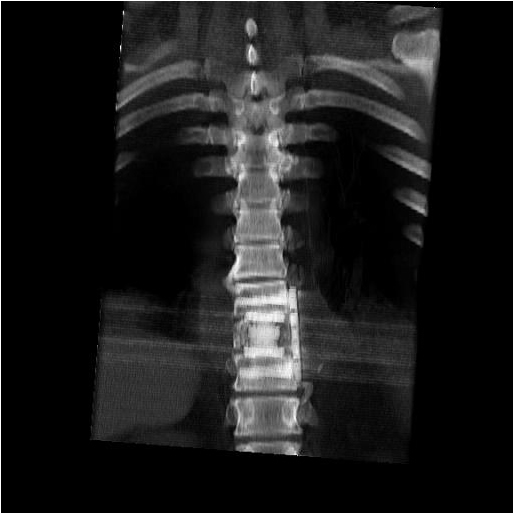

The thoracic spine can be approached through the right or left chest and communication with the spine surgeon is mandatory so that the approach and extent of exposure can be tailored appropriately. In the absence of lateralizing pathology, either a right or left-sided thoracotomy can be used to expose the thoracic spine. As a general rule, the upper thoracic spine (T2-9) is better approached from the right side because of the location of the heart, aortic arch and great vessels. Conversely, in the case of the thoracolumbar spine (T10-L2) a left-sided thoracotomy is preferred to avoid liver retraction. The side of approach must provide maximum exposure to the pathology to be treated. Local factors such as previous thoracotomy, pleurodesis, or infection should also be considered. In general, a right sided approach provides more direct access to the spine, as the mediastinal structures lie to the left of the vertebral bodies. CT and MRI allow for a precise evaluation of the anatomy of the spine pathology and the related intra-thoracic structures (Figures 1a, 1b).